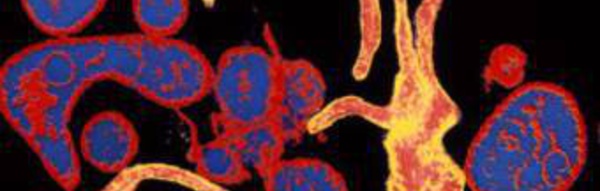

Epidémie de rougeole en Guinée

Une épidémie de rougeole sévit à dans la commune urbaine de Gaoual, située à 397 kilomètres de Conakry la capitale guinéenne. La ville de Gaoual et trois autres villages ont enregistré deux décès sur les 73 malades, pour la plupart des enfants de moins de cinq ans. La campagne de vaccination lancée contre la rougeole est...